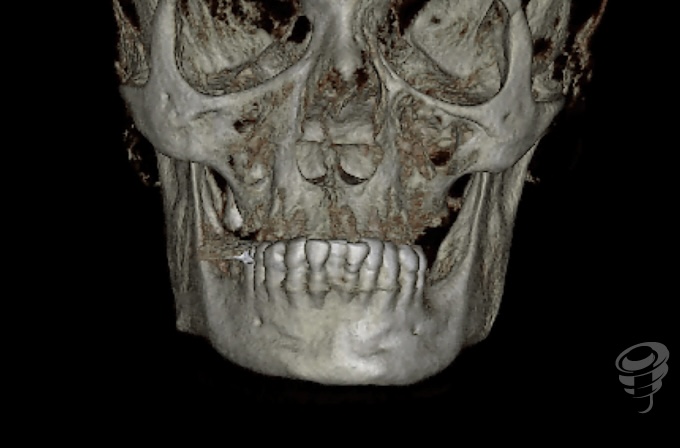

Protocolo Quad Zygoma. (Imagen 26-37)

Por otra parte, el Quad Zygoma nos pemite tratar maxilares con atrofia severa, con posibilidad de carga inmediata, ubicando los implantes en posiciones prostodóncicamente adecuadas que permiten una rehabilitación y mantenimiento convencionales, siendo muy importante para esta técnica evaluar la disponibilidad ósea del cuerpo del cigoma para alojar dos implantes.

Imagen 26 – CBCT Preoperatorio

Imagen 27 – CBCT Preoperatorio

Imagen 28 – Valoración Volumen Cigoma